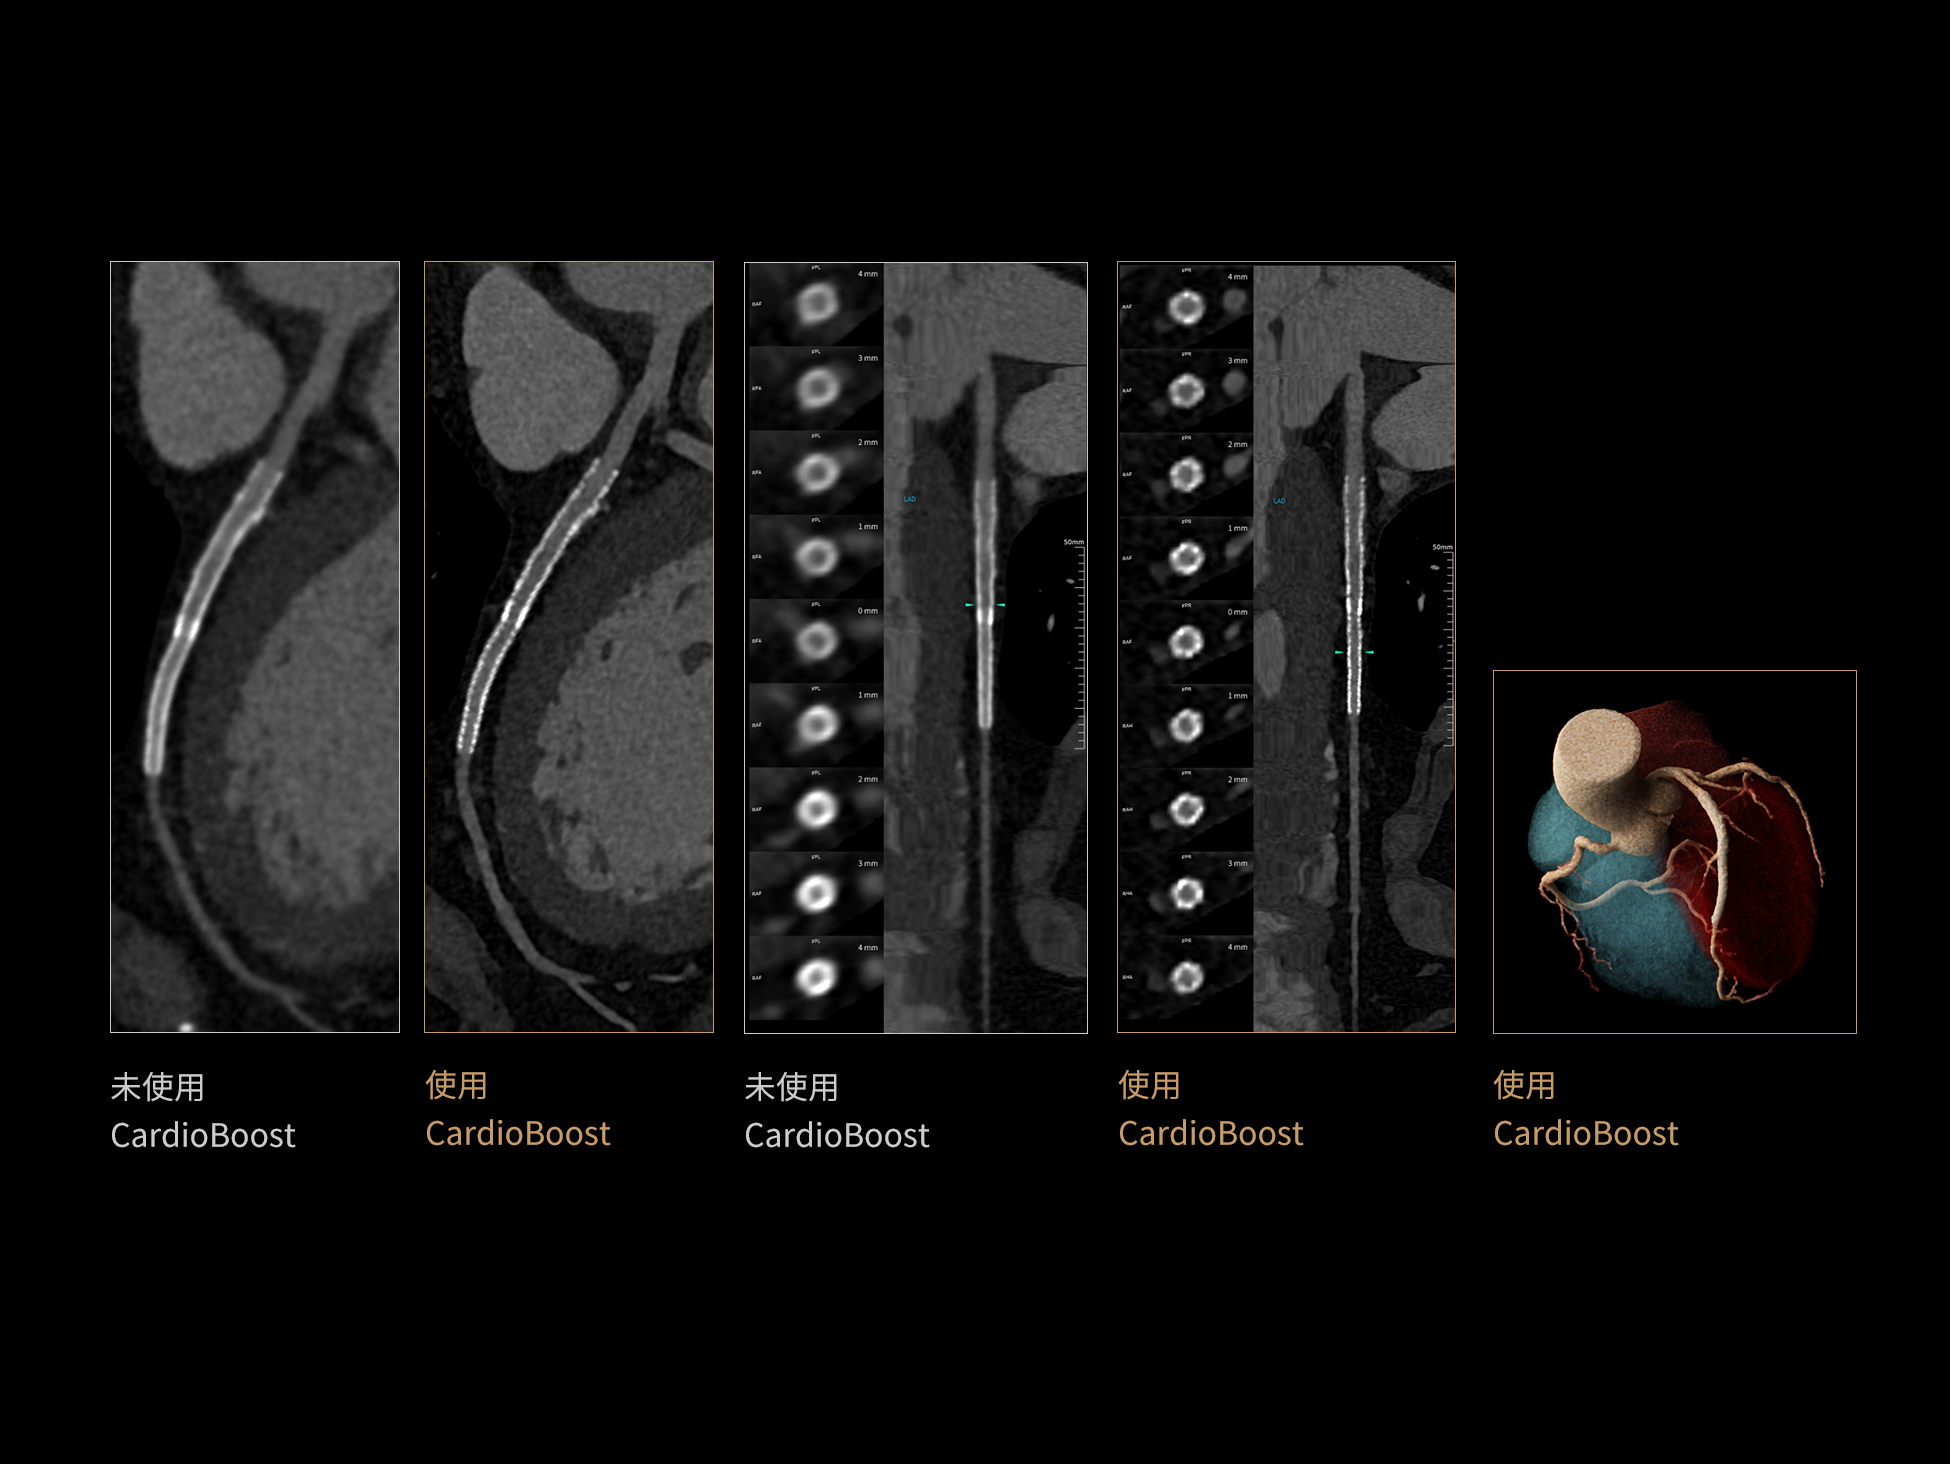

CardioBoost:专属网络设计,重塑心脏影像表现

目前心脏的 CT 检查还存在辐射剂量偏高、空间分辨率不足、 致密钙化伪影影响冠脉狭窄程度评估等方面的限 制[1][2]。CardioBoost 技术专为心脏 CT 高清成像而开发,通过 3D 神经网络的深度学习技术,利用先进的注意力机制在识别关键成像特征方面的出色表现,能够精确地聚焦于斑块、支架以及微小血管等关键细节,清晰展示这些结构与冠脉血管的边界,从而显著提高诊断的准确性,并提升医生的诊断信心。创新的 CardioBoost 心脏图像重建算法,不仅实现了图像清晰度的提升和伪影的去除,更能在减少辐射剂量的同时,保证心脏图像的高质量和图像纹理的自然。

CardioBoost核心创新

采用 3D 神经网络的空间结构优势与精细的组织分类能力,CardioBoost 技术优化了组织对比,高清展示血管斑块,使斑块与血管边缘的轮廓清晰可辨,提升斑块诊断与评估的精确性。

借助 3D 神经网络设计、空间注意力机制聚焦与特征强化作用,CardioBoost技术提升图像的空间分辨率,实现冠脉支架的高清成像,对支架形态与管腔通畅度的评估更精准。

CardioBoost 整合先进的 3D 神经网络和空间注意力机制,大幅增强数据处理的速度与精确度。该技术能有效抑制由致密钙化引起的晕状伪影,清晰展现钙化斑块的原始结构和大小,对冠脉狭窄的评估更加精确可靠。